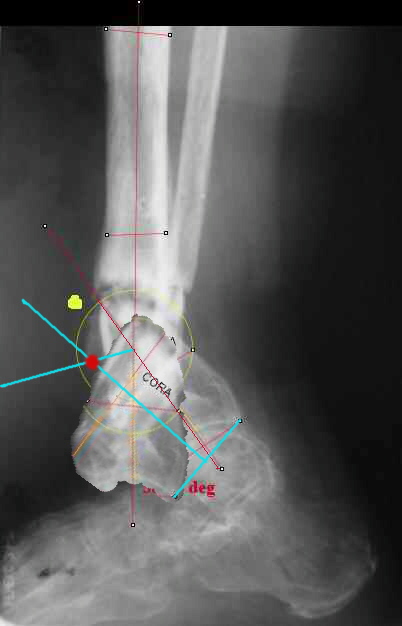

Maybe my "embedded software" is obsolete but it hints me to place hinges at the yellow point - this must result with alignment and some lengthening without translation. What do you think?

Hi Alex:

I looked at your image. I presume your yellow marker is the hinge axis? I think this should be at the CORA.